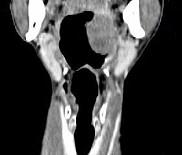

问题 男,67岁,口咽部异物感约8个月,伴口咽部疼痛,患者无明显发热.如图所示最可能的诊断为()

选项 A.扁桃体结核伴淋巴结转移 B.扁桃体脓肿伴淋巴结转移 C.扁桃体癌伴淋巴结转移 D.扁桃体淋巴瘤 E.下咽癌伴淋巴结转移

答案 C